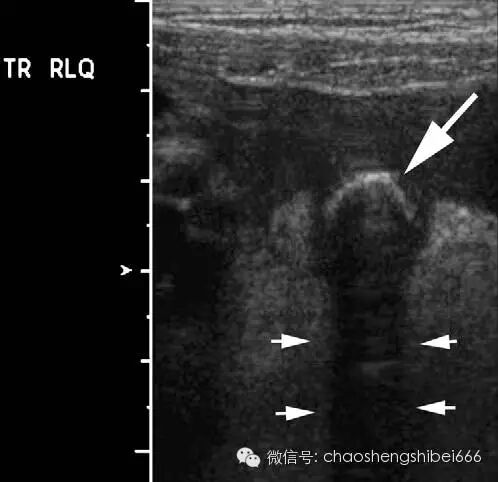

Puylaert在1986年首次提出超声探头逐级加压的方法诊断阑尾炎。如前所述使用线阵探头,逐步缓慢的加压以提高病人的耐受性。检查最好以问病人“你哪儿痛?”开始(而不是让病人指出疼痛的具体点)。无并发症的阑尾炎患者通常会指出疼痛具体位置。根据其指出的方位即是扫查的起始位置。患者指出疼痛部位的深方,常常会令人吃惊的发现病变阑尾。如果没有当即找到阑尾,就要对右下腹及盆腔进行全面系统的扫查,并且分别在横切面及纵切面摆动探头仔细扫描。经验不足的超声工作者经常因为没有足够的探头加压扫描而造成漏诊。足够的压力可以使后腹壁、腰大肌及髂血管显示(图1)。在Puylaert的文章中,插图清晰的反映了所需加压程度。

图1 15岁右下腹痛女孩的超声图像。后腹壁包括腰大肌(P)的显示表明加压充分。箭头表示前腹壁的腹直肌(R)与后腹壁的腰大肌之间被压的距离很小。